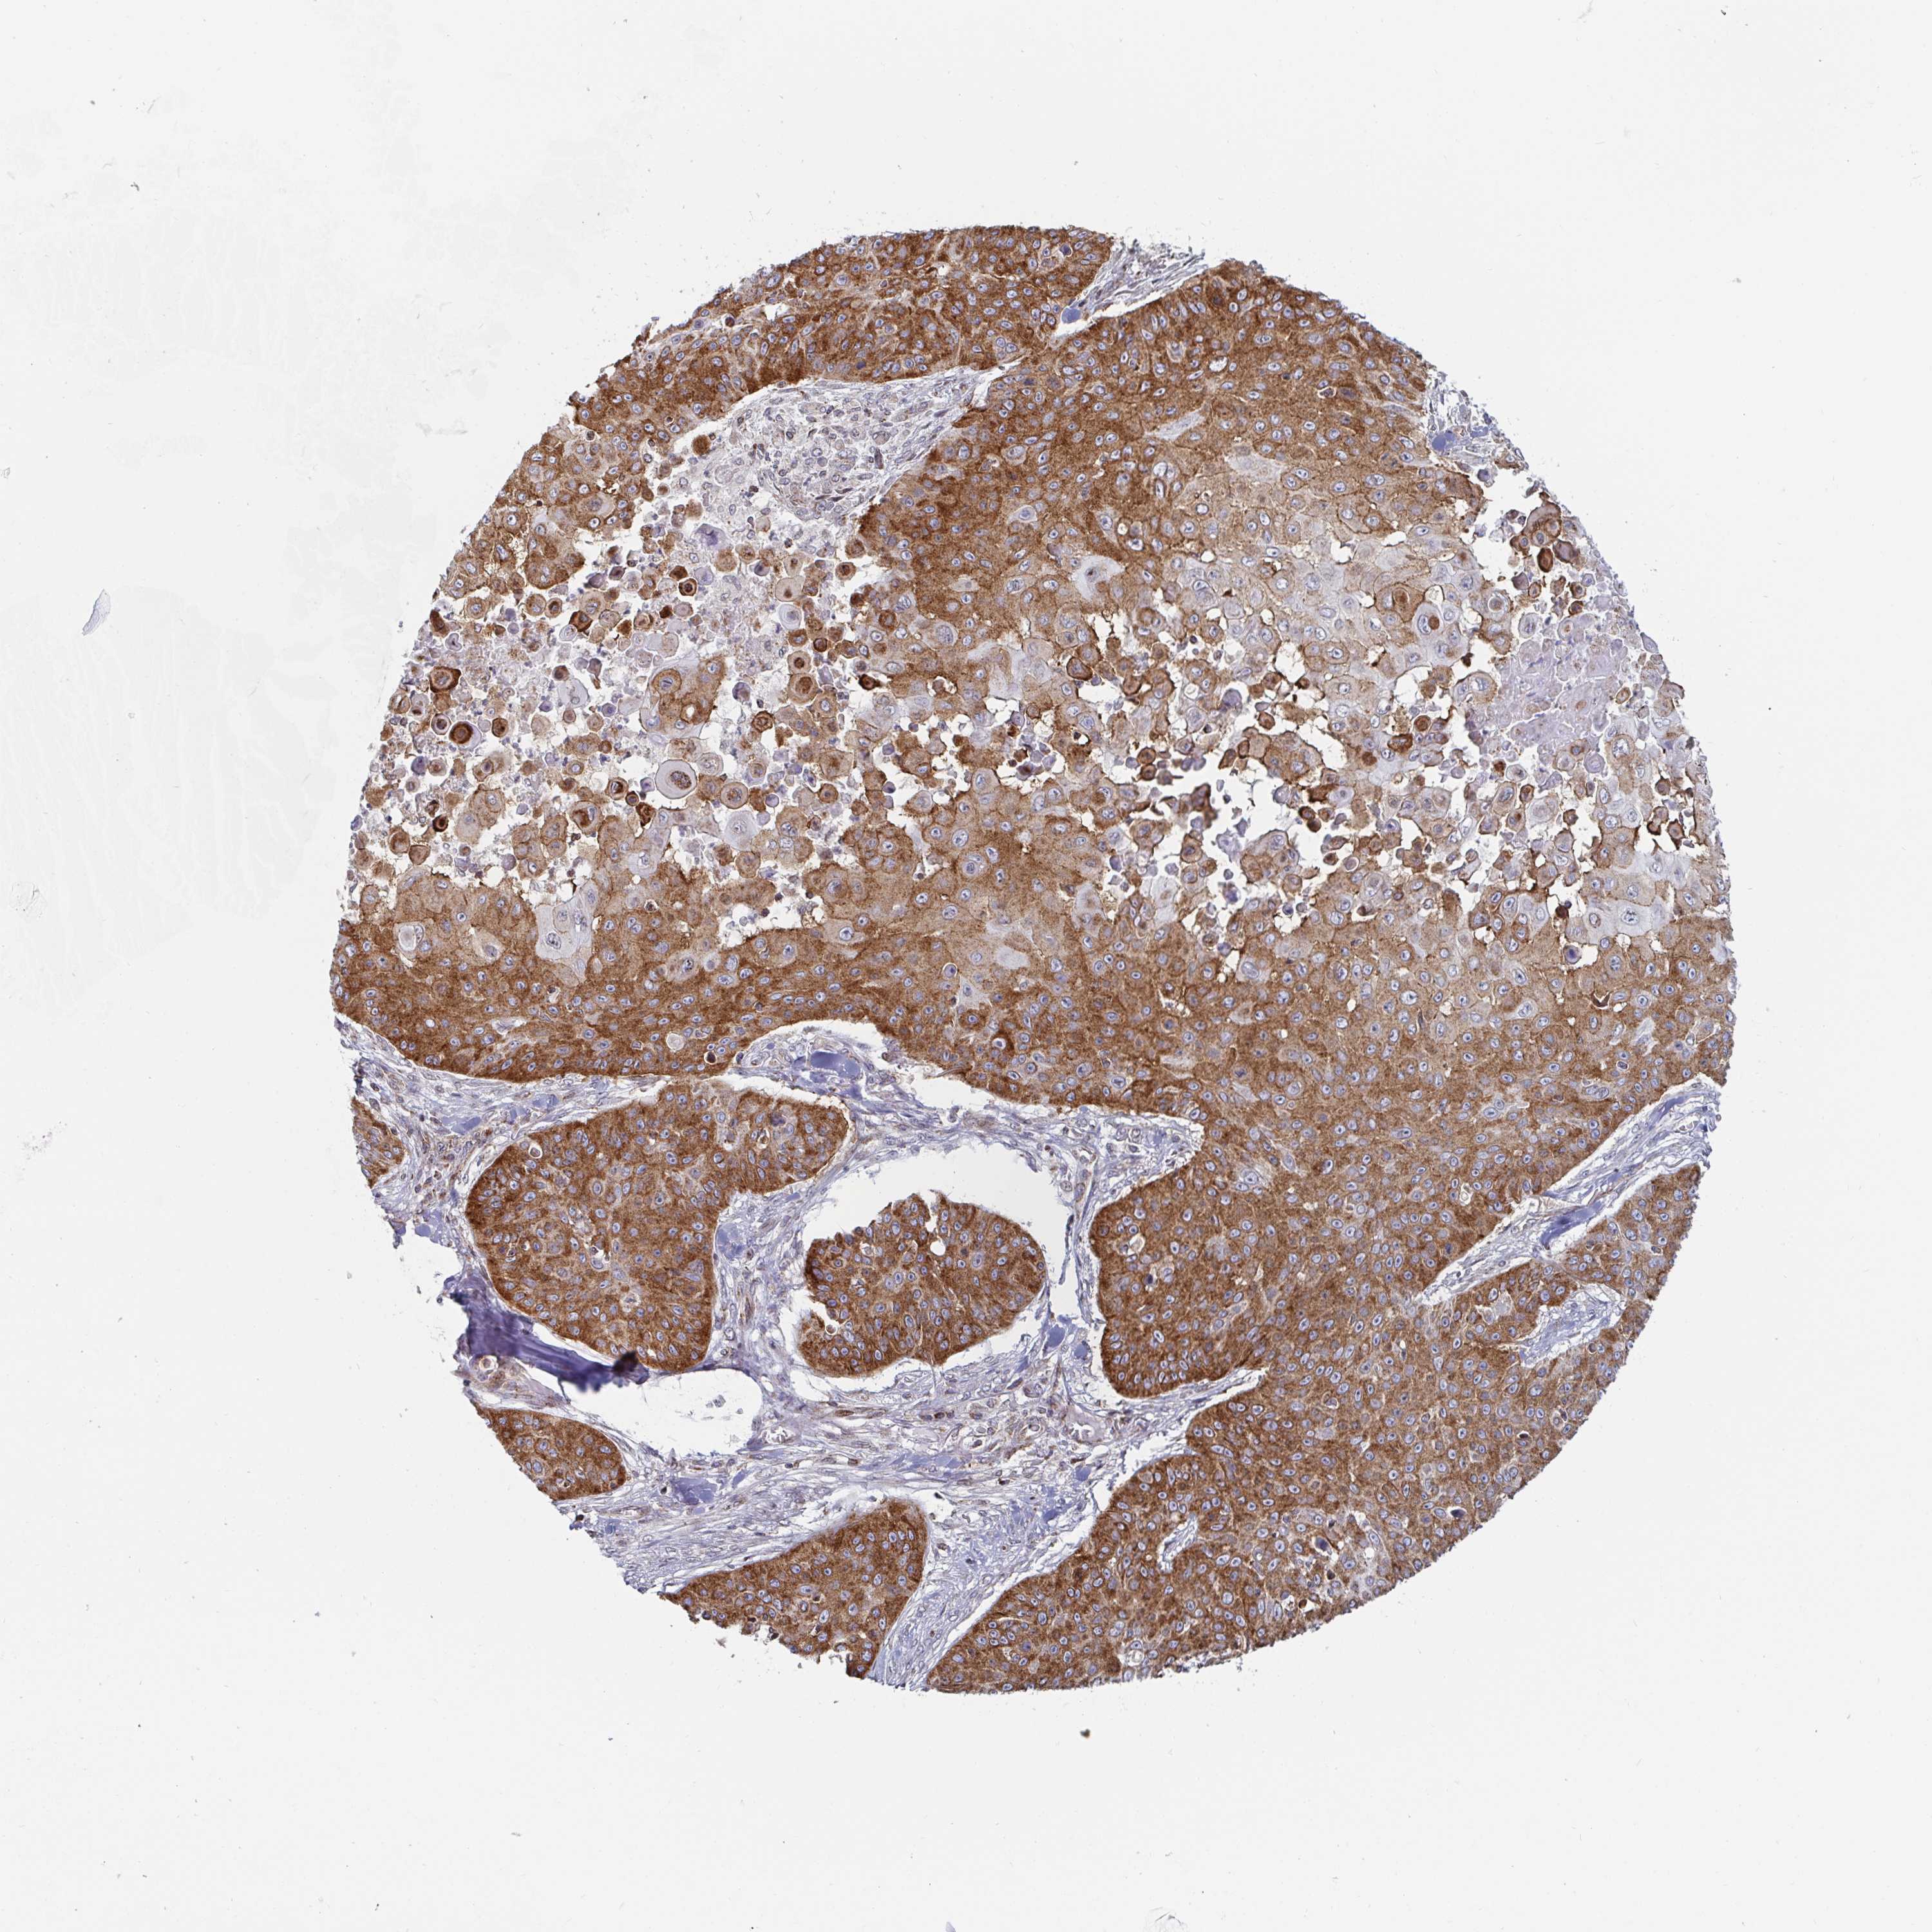

SKIN CANCER - Protein expressioni

A mouse-over function shows sample information and annotation data. Click on an image to view it in a full screen mode. Samples can be filtered based on level of antibody staining by selecting one or several of the following categories: high, medium, low and not detected. The assay and annotation is described here.

Antibody stainingi

Antibody staining in the annotated cell types in the current human tissue is reported as not detected, low, medium, or high, based on conventional immunohistochemistry profiling in selected tissues. This score is based on the combination of the staining intensity and fraction of stained cells.

Each image is clickable and will lead to virtual microscopy that enables deeper exploration of all samples and also displays staining intensity scores, fraction scores and subcellular localization as well as patient and tissue information for each sample.

Antibody HPA060788

Staining

High

Medium

Low

Not detected

Intensity

Strong

Moderate

Weak

Negative

Quantity

>75%

75%-25%

<25%

None

Location

Nuclear

Cytoplasmic/membranous

Cytoplasmic/membranous,nuclear

Basal cell carcinoma

BCC, high aggressive

Squamous cell carcinoma, NOS